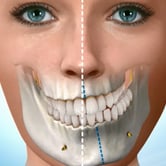

Ortognática (cirugía correctiva de mandíbula)

La cirugía ortognática corrige anomalías en los huesos de la mandíbula y el maxilar que afectan la mordida y la estética facial.

Los pacientes pueden notar dificultades para masticar, hablar y una apariencia facial desproporcionada.

El tratamiento incluye la planificación prequirúrgica y la cirugía para reposicionar los huesos.